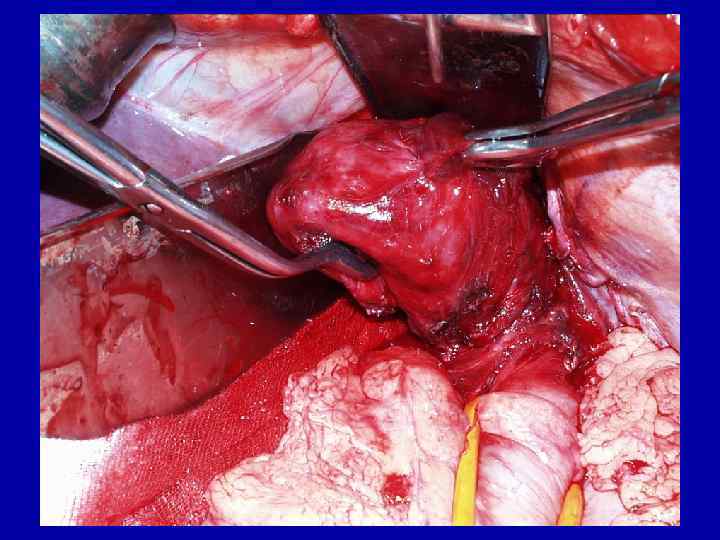

Больная К. , 56 л. Ds: кардиоспазм IV стадии 10. 09. 03 – экстирпация пищевода с одномоментной пластикой желудочной трубкой

Экстирпация пищевода 35 см